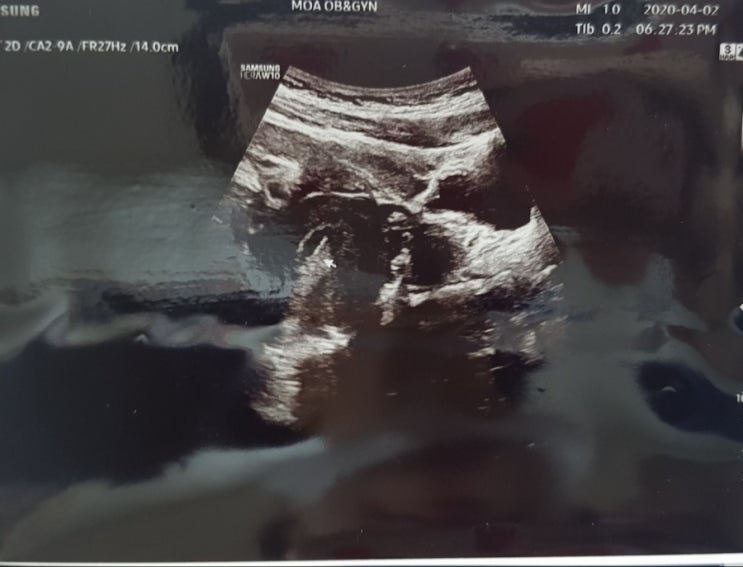

임신 6주-7주 증상 (4월 10일-4월 23일) 4월 16일은 쩨리 심장소리를 들으러 가는 날이였다..! 4월 7일 설...